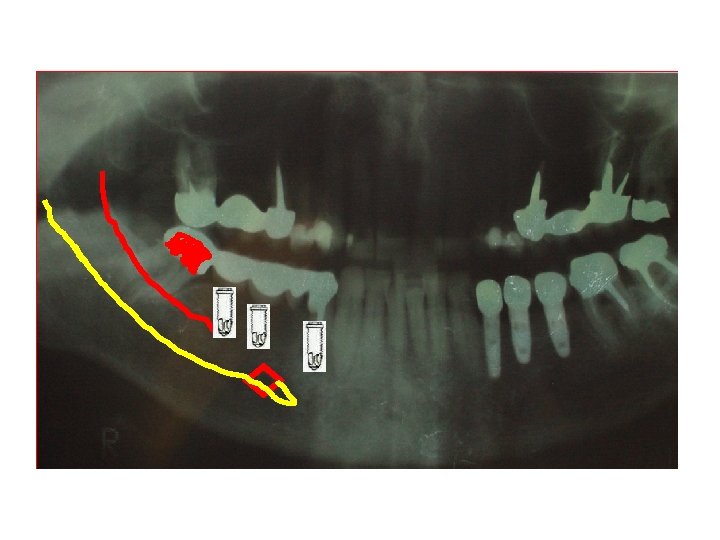

TEMPLATE PRÉOPERATÓRIO – SOBRE PANORÁMICA P 11 MAGNIFICAÇÃO REGULAR DE 30%

ROMPIMENTO ALVEOLAR INFERIOR TEMPLATE PRÉ-OPERATÓRIO – SOBRE PANORÁMICA P 11 MAGNIFICAÇÃO REGULAR DE 30%